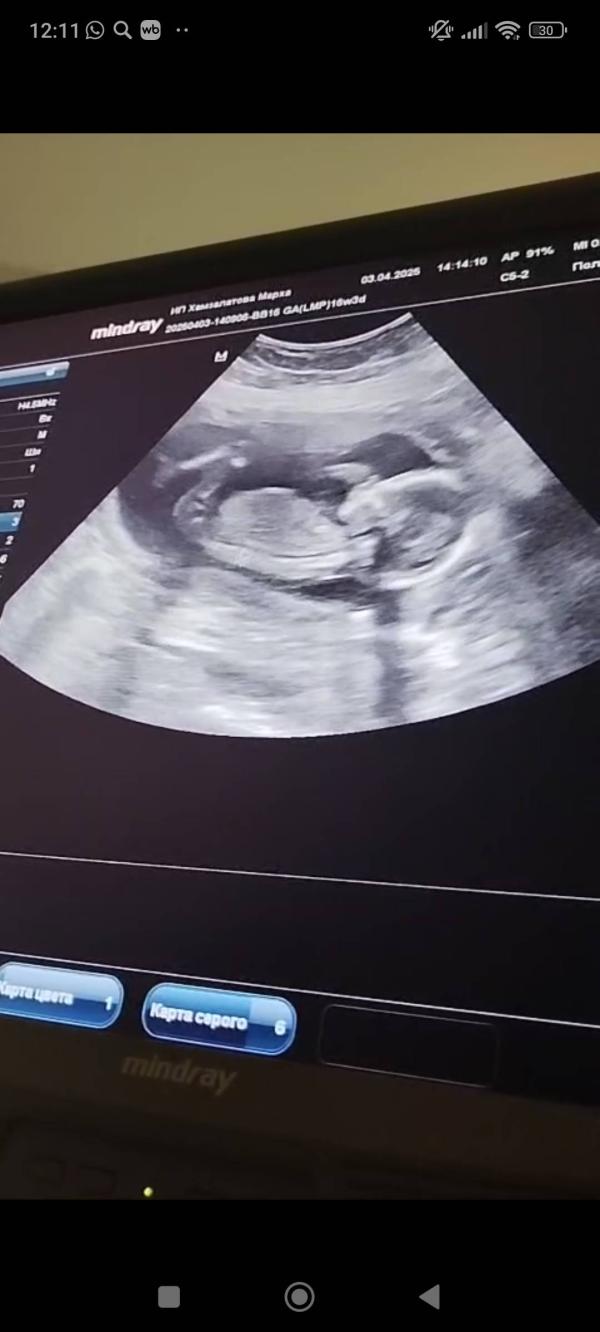

Как думаете мальчик или девочка?

@sss2206gmail по этому фото мальчик

Просто по ощущениям это девочка 😀🌸

Я за девочку 😂